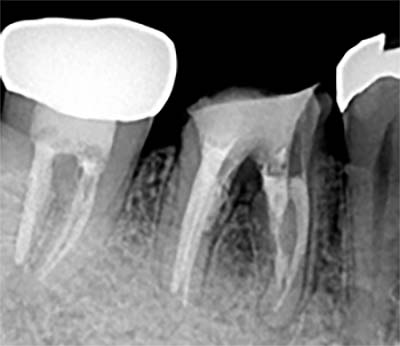

根尖封鎖の比較

![]() |

| MTA根充前 | MTA根充後 |

MTA / バイオセラミックによる3次元根尖封鎖

根の先端に行う“根尖封鎖”は、治療の成否を左右する超重要工程です。

| MTA充填前 | MTA充填後 |